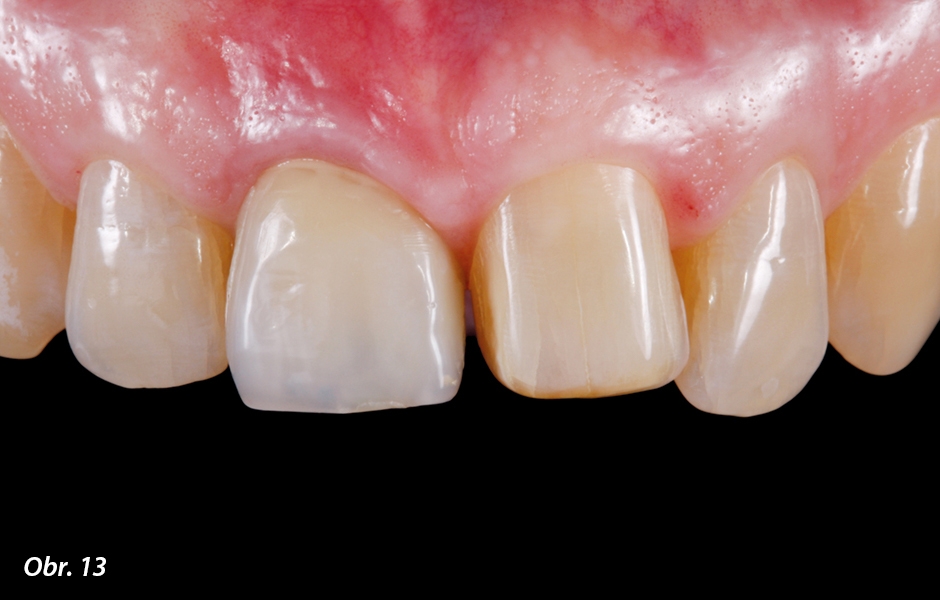

Klinická výchozí situace jasně ukazuje, že na pacientčině levé straně se střední horní řezák jeví příliš krátký ve srovnání s průběhem incizní hrany postranního řezáku (viz obr. 1). Tento stav obtěžoval pacientku již delší čas. Proto pro ni bylo velmi důležité esteticky tuto situaci řešit a spolu s korunkou na implantátu korigovat i nedostatek vertikálního rozměru klinické korunky zubu 21. Za tímto účelem byl preparován levý střední řezák na minimálně invazivní keramickou fazetu (obr. 12, 13).

Horní levý střední řezák byl kvůli optimalizaci tvaru a délky obou středních řezáků napreparován na minimálně invazivní fazetu. Hloubkovým značkovačem byla stanovena nepatrná labiální hloubka preparace.

Dokončená preparace na fazetu s incizálním schůdkem za účelem prodloužení zubu pomocí keramické fazety